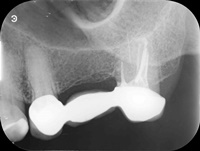

Reendo dolnej szóstki.

Wykonany zabieg resekcji wierzcchołka nie pomógł w ustąpieniu obajawów zapalnych. Skuteczne okazało sie dopiero reendo.